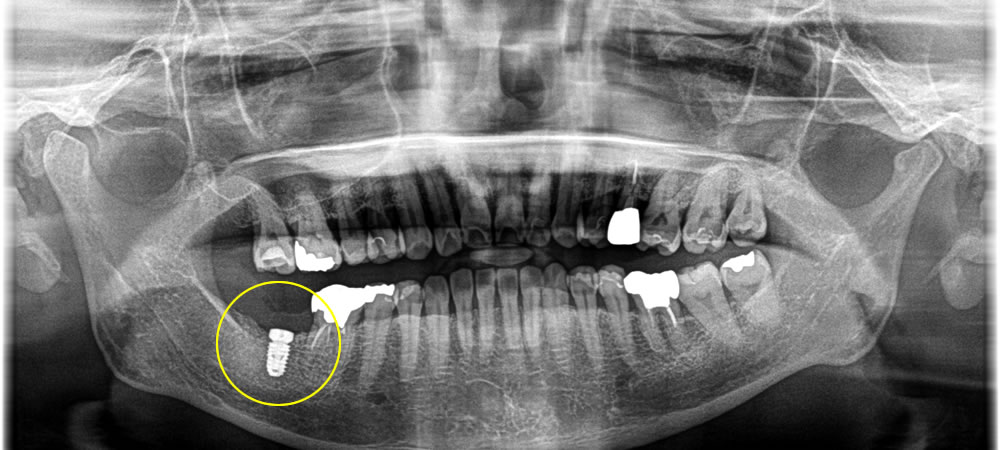

骨欠損が大きかったため、インプラントの埋入と同時に骨造成も行い、減張切開にて完全クローズの2回法で治療を行いました。